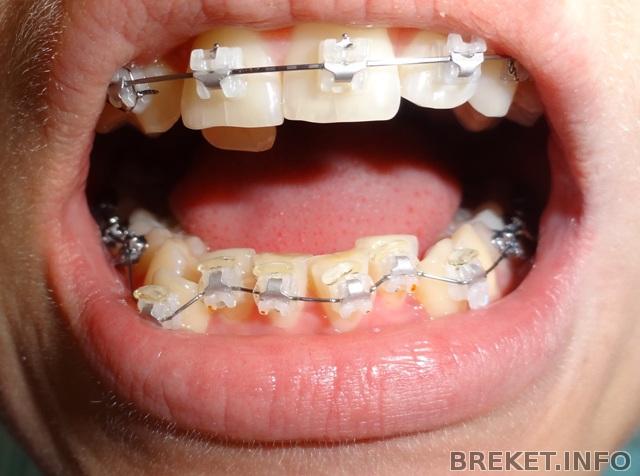

сегодня поставили на нижнюю челюсть, а верхнюю облепили какими-то железными цепями

Когда орт. дала мне зеркальце, я довольно затяжно промолчав сказала "какой ужас!"

и действительно - ужас.

когда я пришла домой я смотрела в зеркало и мне стало жутко смешно: я похожа на акулу и на железного человека одновременно.

Сегодня неожиданно для меня моя ортодонт предложила мне зафиксировать низ- "если конечно Вы не торопитесь"- улыбнувшись произнесла она. Я , конечно, согласилась, т.к. в нашем деле чем быстрее,тем лучше))) Длилось всё около 40 минут, ну,собственно как и с ВЧ. Через несколько дней удаление 4-ок нижних, боюсь до жути, хотя уже удадляла на ВЧ, но всё равно боюсь))). На ВЧ дугу оставила ту же, но , хвала моим дотошным просьбам и мольбам, стянула клыки и 5-ки лигатурками. Фото, как всегда прилагаю.